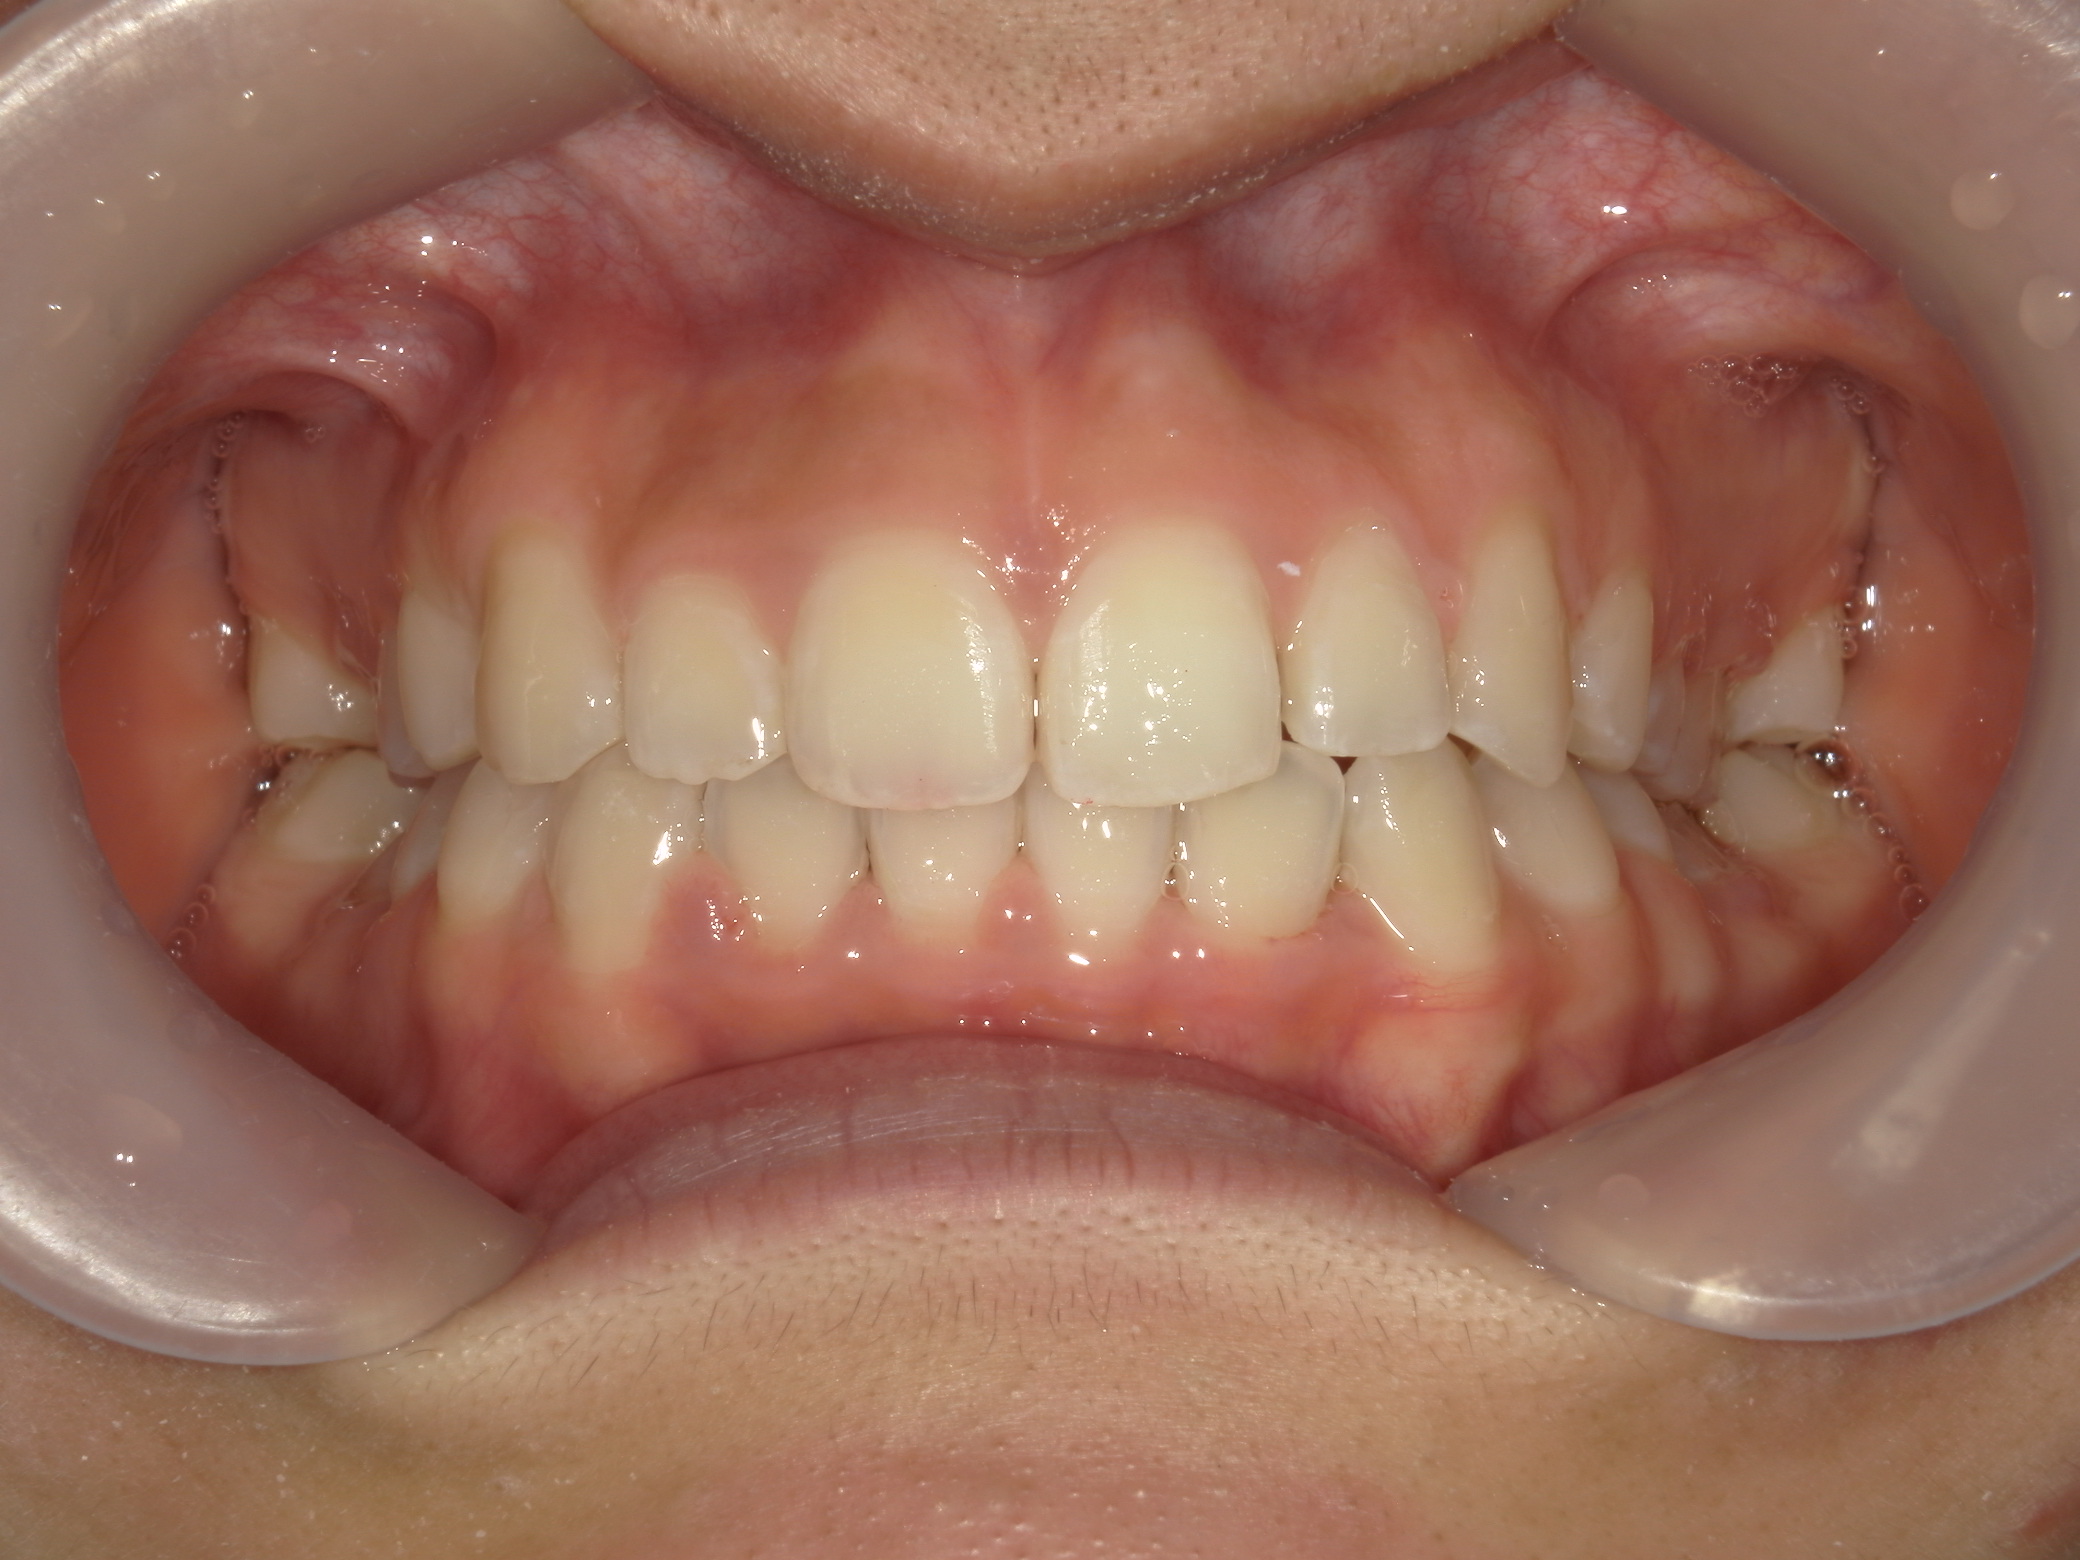

プチワイヤー矯正 症例(54)

主訴: 歯並びが気になる。

カテゴリー : ガタガタ(叢生)